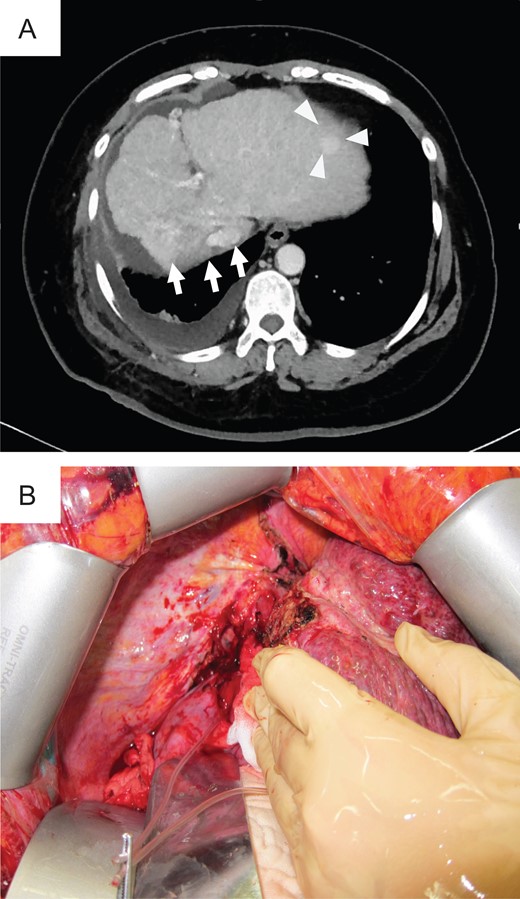

The patient was a 60-year-old man who had been diagnosed with HCV-related LC and HCC (Table 1). In 2014, this patient underwent CIRT with a total of 60 Gy (relative biological effectiveness) given in four fractions for HCC in S4 and was in complete remission (CR). In 2015, multiple HCC was observed on CT (Fig. 3A). After treatment with TACE, he met the Milan criteria and underwent LT. Preoperative magnetic resonance imaging with gadolinium-ethoxybenzyl-diethylenetriamine penta-acetic acid (EOB-MRI) revealed atrophy in the CIRT area and hypertrophy in the left liver (Fig. 3B).

Preoperative photograph and intraoperative images of case 2. (A) New lesion in S6 on preoperative CT. Atrophy was noted in the CIRT area, and hypertrophy was noted in the left liver on preoperative EOB-MRI (B) and intraoperative images (C). (D) Severe tissue adhesion on the hepatic hilar resulted in difficulties during adhesiolysis.

During surgery, strong atrophy of the liver parenchyma was found in the irradiated area (Fig. 3C). Tissues adjacent to the irradiated area were also strongly adhered. During dissection of the right side in the liver hilum, the right hepatic artery (RHA) was injured due to inflexible conglutination (Fig. 3D). We sutured and closed the bleeding point of the RHA and decided to separate the RHA without detachment between the RHA and bile duct. Carefully, the liver was retrieved after we successfully secured the common bile duct, left hepatic artery (LHA), PV and HV. This case is also transplanted with left lobe graft. We reconstructed the middle hepatic vein and left hepatic vein (MHV–LHV) in the recipient to the MHV–LHV in the donor by continuous sutures with 4-0 Prolene, the left branch of the PV in the recipient to the left branch of the PV in the donor by continuous sutures with 5-0 Prolene, and the LHA in the recipient to the LHA in the donor by interrupted sutures with 8-0 Prolene using microscopy.